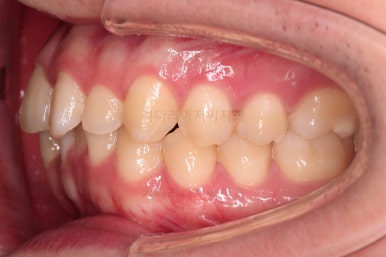

부산교정치과 초진 시 입안의 모습입니다.

앞니가 삐뚤어서 결손치아가 없었더라도 교정치료를 원하셨던 상황이었고요.

오른쪽 어금니 맞물림은 결손치아도 그렇지만 전반적인 앞뒤 차이가 있는 부정교합이 있었어요.